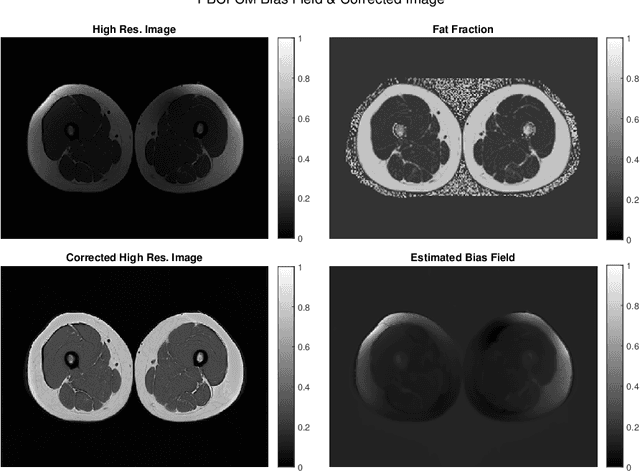

Abstract:Image segmentation is a complex mathematical problem, especially for images that contain intensity inhomogeneity and tightly packed objects with missing boundaries in between. For instance, Magnetic Resonance (MR) muscle images often contain both of these issues, making muscle segmentation especially difficult. In this paper we propose a novel intensity correction and a semi-automatic active contour based segmentation approach. The approach uses a geometric flow that incorporates a reproducing kernel Hilbert space (RKHS) edge detector and a geodesic distance penalty term from a set of markers and anti-markers. We test the proposed scheme on MR muscle segmentation and compare with some state of the art methods. To help deal with the intensity inhomogeneity in this particular kind of image, a new approach to estimate the bias field using a fat fraction image, called Prior Bias-Corrected Fuzzy C-means (PBCFCM), is introduced. Numerical experiments show that the proposed scheme leads to significantly better results than compared ones. The average dice values of the proposed method are 92.5%, 85.3%, 85.3% for quadriceps, hamstrings and other muscle groups while other approaches are at least 10% worse.